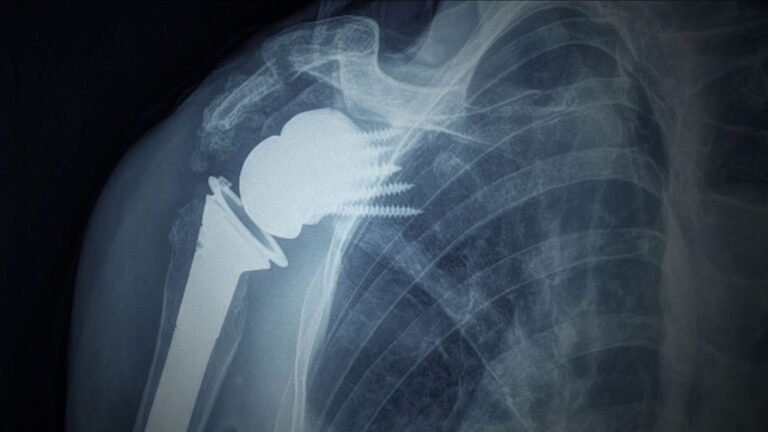

Mysuru, November 2025: In a remarkable leap for medical innovation, JSS Hospital has successfully conducted a Reverse Total Shoulder Arthroplasty (RTSA) using Virtual Implant Positioning (VIP) technology. This marks a groundbreaking moment in orthopaedic surgery, showcasing how advanced digital tools can enhance surgical precision and patient recovery.

Reverse Total Shoulder Arthroplasty (RTSA) is a specialized procedure for patients suffering from irreparable rotator cuff tears, shoulder arthritis, or pseudo-paralysis—conditions where traditional shoulder replacement often fails. In RTSA, the natural ball-and-socket structure of the shoulder is reversed: the ball is placed on the shoulder blade, and the socket is fixed to the upper arm bone.

This unique design allows the deltoid muscle to compensate for damaged rotator cuff tendons, restoring strength and function to the shoulder. The technique significantly improves mobility and enables patients to perform daily activities like reaching overhead or combing hair—tasks often impossible before surgery.